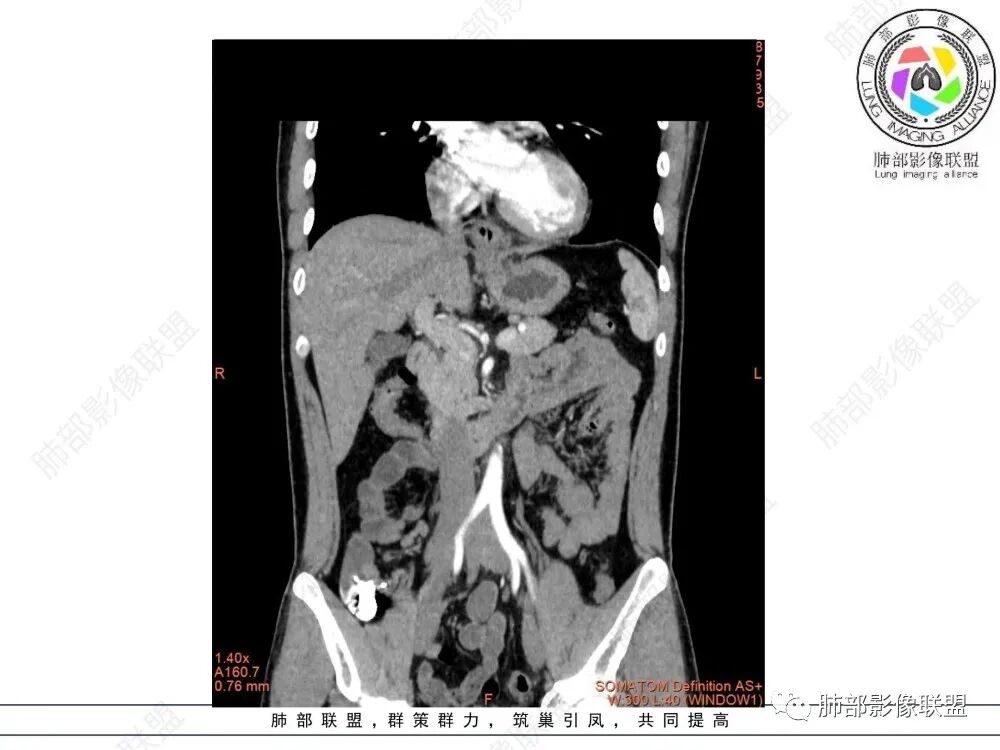

影像学特点:类纵隔区病变,沿食管生长,形态不规则,但边界清楚,内部信号/密度均匀,强化程度比较弱。

影像诊断思路:起源食管肿瘤(非黏膜起源,肌层起源),良性或低度恶性肿瘤可能性大,一般以神经鞘瘤、胃肠间质瘤及平滑肌瘤为主。食管神经鞘瘤强化明显均匀、以食管上段多见,周围常见炎性增大淋巴结,不太符合;胃肠间质瘤小的比较均匀,大的不均匀,但强化程度较高;影像上看这例病例比较符合平滑肌瘤。

食管平滑肌瘤是最常见的食管良性肿瘤,多见于男性,男女之比为2.6:1,高发年龄 30~60岁之间与食管癌相比,食管平滑肌瘤 的一个主要特点是病史相对较长,病情进展缓慢。病史最长者达10年余,平均 15.7个月,尽管病史较长,但大多数患者仍能进普食。食管平滑肌瘤的诊断一般比较容易,结合患者临床症状、食管造影及食管镜所见,一般均能得出正确诊断。食管造影主要为充盈缺损,病变与食管壁成锐角,粘膜线连续无破坏,管腔收缩扩张比较自如。钡餐造影敏感性高,但对食管壁间及食管周围情况难以判断。CT具有极高的密度分辨率,并且可以获得高质量的多平面重组图像,有利于食管壁间及食管周围情况的判断,表现为食管下段环绕管壁生长,偏心性或薄厚不均软组织密度肿块,密度均匀,内缘分叶状,管腔与正常食管壁构成不规则多角形扩张,增强动脉期无强化,多角度重建其病灶长轴与食管长轴不一致。由于食管壁在收缩状态下厚度约为5.6mm,扩张状态厚度不超过3mm,CT扫描时保持食管处于扩张状态可提高小病灶检出率。MR表现为T1加权等信号,T2加权稍高信号,可见高信号粘膜层,增强扫描轻度渐进性强化,密度均匀,无出血坏死。对于粘膜及周围脂肪间隙的判断具有明显优势。